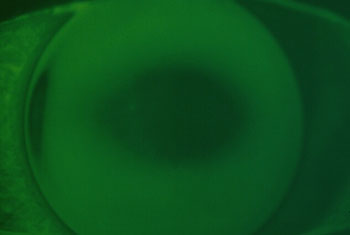

| Fluobildb, Grad +2: |

Eine sehr flache Auflage ist gekennzeichnet

durch eine zentrale Auflage (erscheint dunkel). Die Peripherie der

Kontaktlinse steht weit ab.

Häufig kommt es bei einer solchen Flachanpassung zu starken Dezentrierung. |